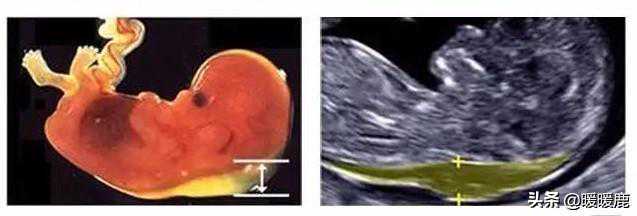

1、胎儿颈项部透明层(NT)NT是“胎儿颈项部透明层”的英文缩写,是指胎宝宝颈背部的皮下积液厚度。孕妈一般会在孕11~13周做NT检查时,如果NT值≥2.5mm代表NT增厚,且NT越厚,胎儿患有染色体异常和畸形的几率越大,这时就要通过无创DNA或羊水穿刺进一步排查胎儿染色体异常的问题。另外还要结合孕中期的系统B超、四维彩超和胎儿心脏超声等检查,对胎儿进行全面评估。做了NT还要做唐筛吗?无创和羊水穿刺又是怎么回事?做了NT,还需要做无创DNA或羊水穿刺吗?

唐氏筛查NT